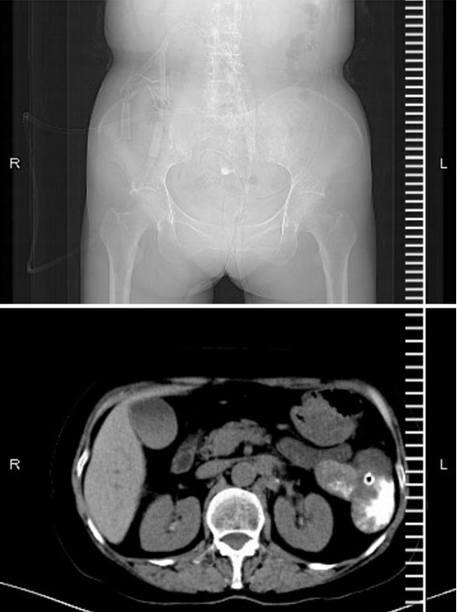

入院后请内镜中心协助经内镜下放置经肛门肠梗阻导管,肠镜进镜至距肛缘40cm降结肠处肠腔扭曲,粘膜水肿,无法继续进镜,X线下造影观察狭窄长度约1cm。狭窄近端肠腔扩张明显,内镜钳置入胆道导丝通过狭窄段至横结肠,退镜后留下导丝,循导丝置入经肛门肠梗阻导管至横结肠近端。肠梗阻导管置入成功后,每日予以经肠梗阻导管灌肠,充分减压,再次行CT检查发现减压效果良好(图2所示:图2上为平片显示梗阻缓解,图2下为肠梗阻导管通过降结肠肿瘤进入近端肠管减压)。

图片

图2